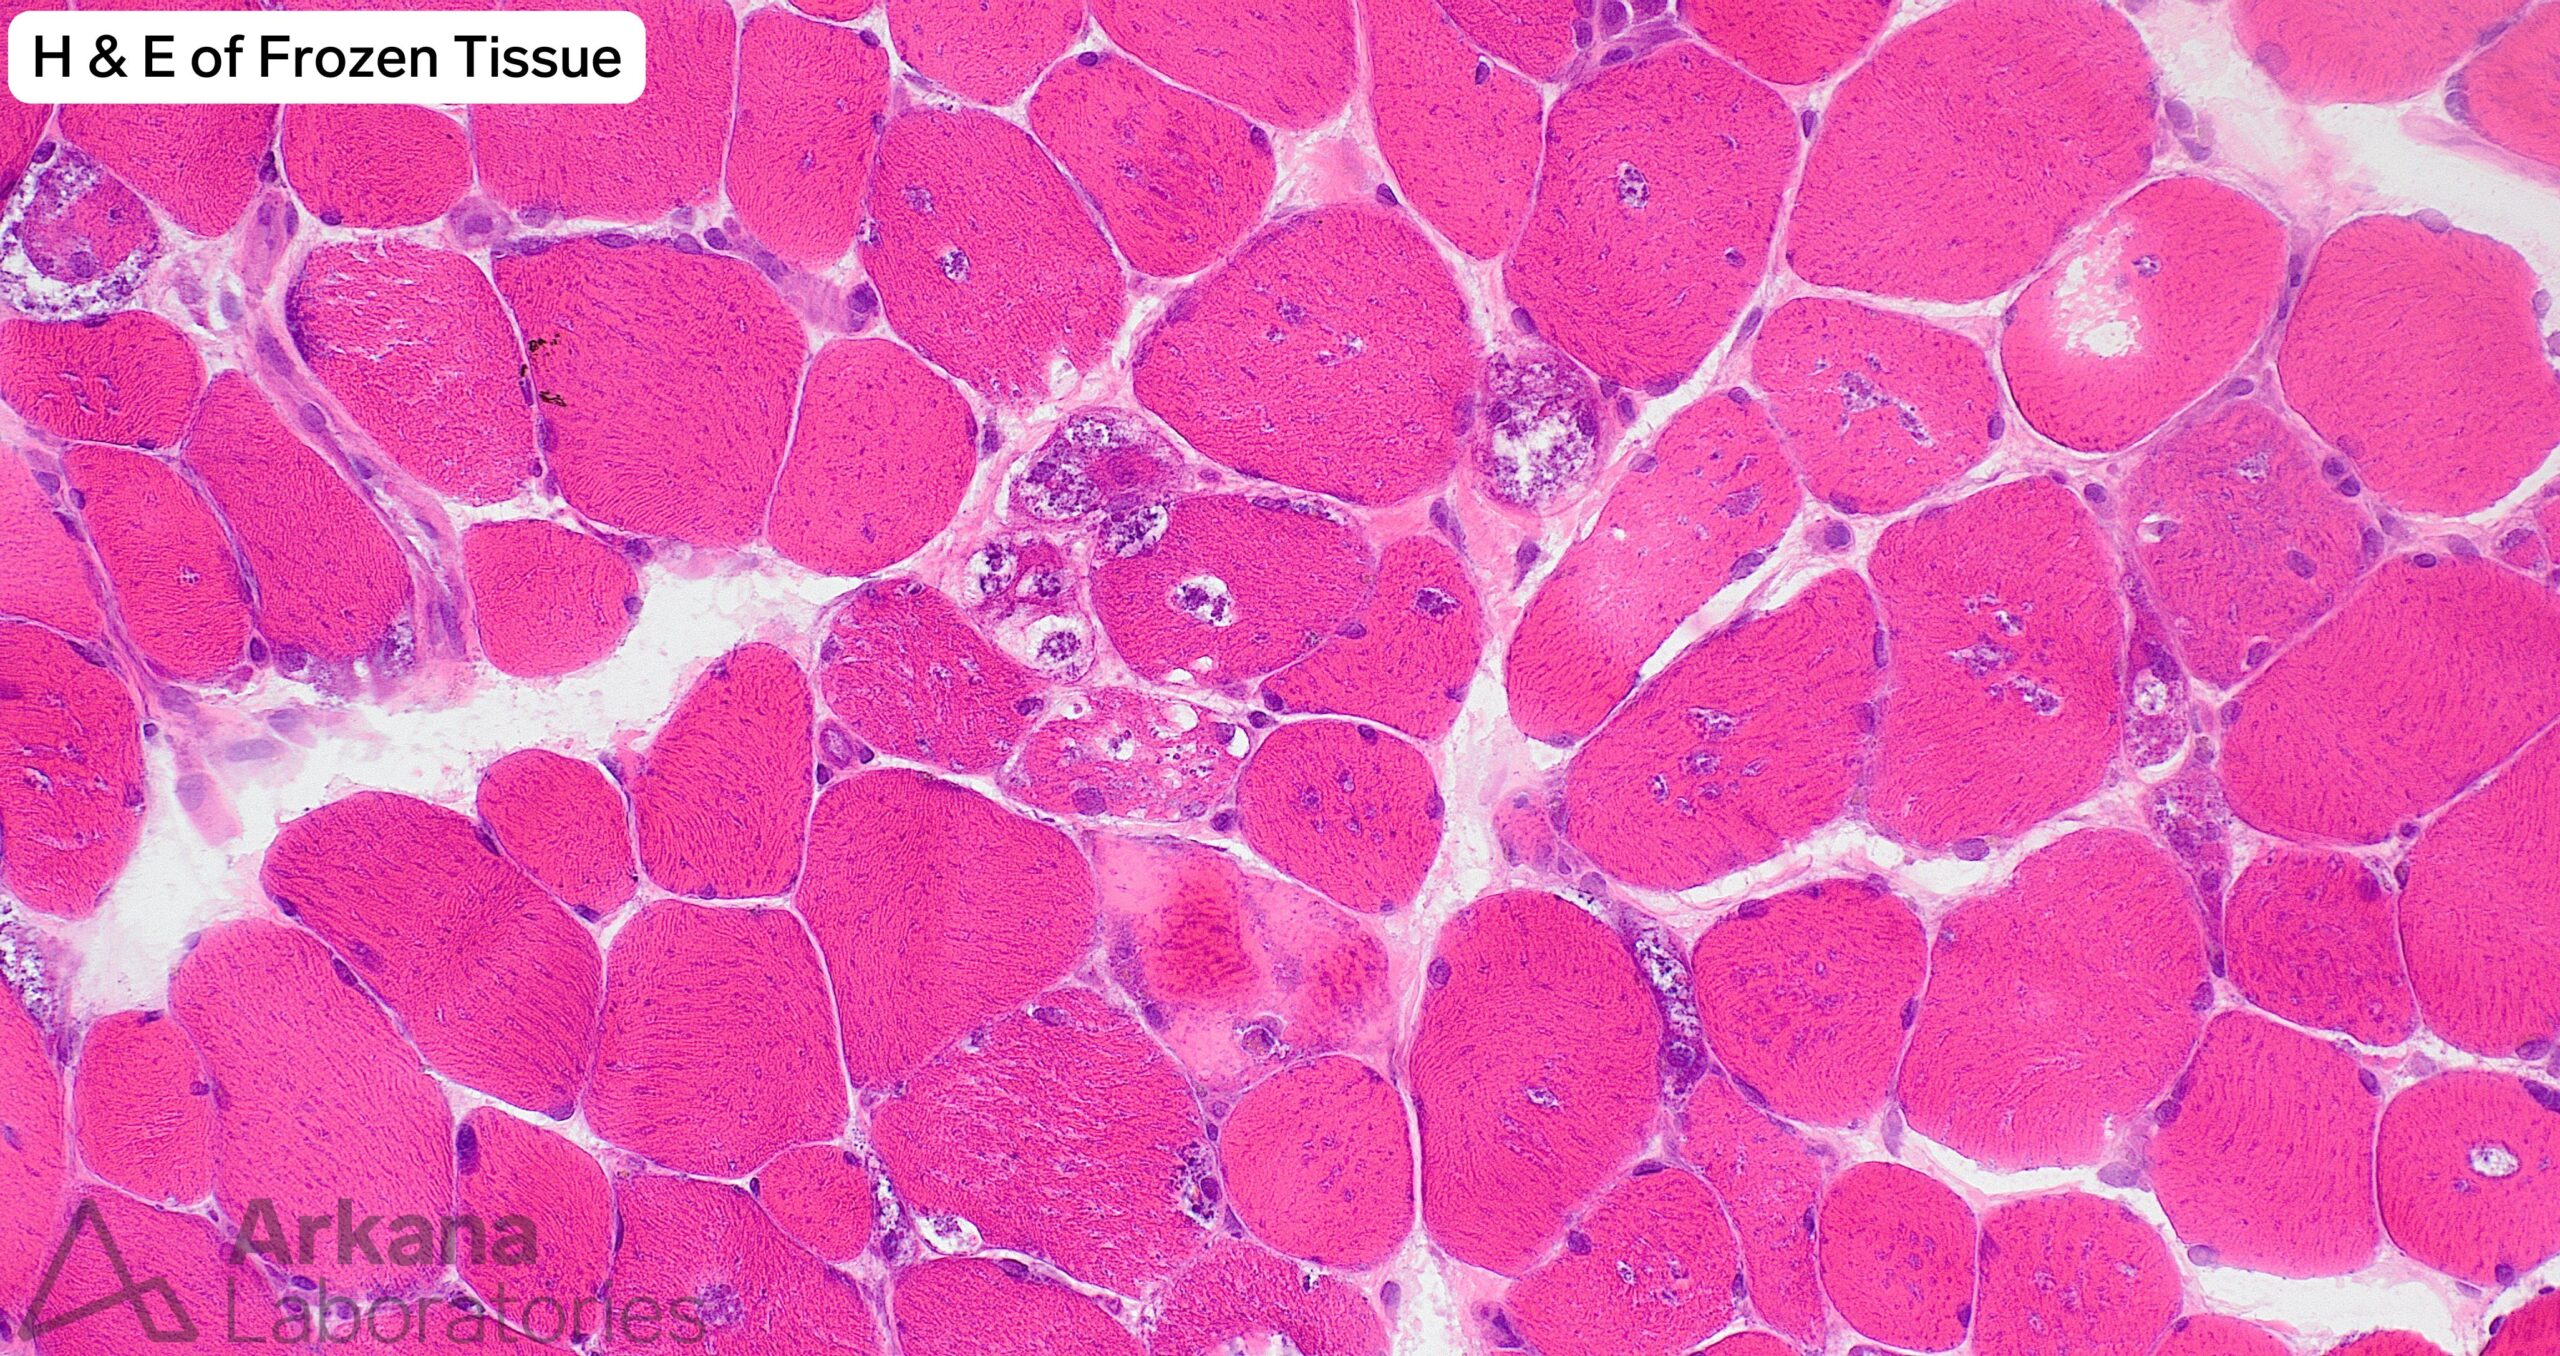

Vacuolar Myopathy Due to Hydroxychloroquine Toxicity

- The presence of a vacuolar myopathy is well-demonstrated on frozen section H&E and modified Gomori Trichrome stained sections. Acid phosphatase preparation shows increased lysosomal type staining within myofiber.